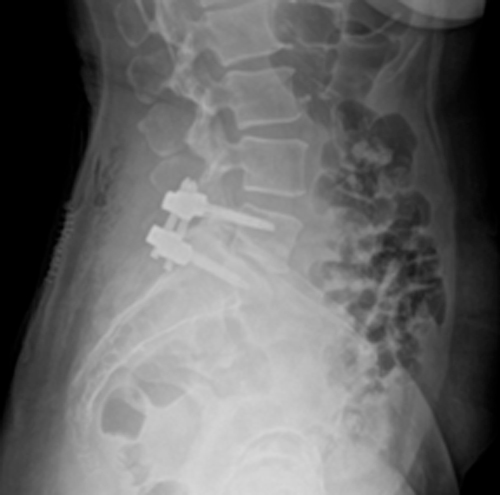

DIAGNOSI:

SPONDILOLISTESI CON STENOINSTABILITA’ L3-L5

Radiografia lombare pre-operatoria

Intervento chirurgico eseguito:

Artrodesi lombare mediante viti transpeducolari L3-L4-L5 + introduzione di cage intersomatica plif

Radiografia post-operatoria